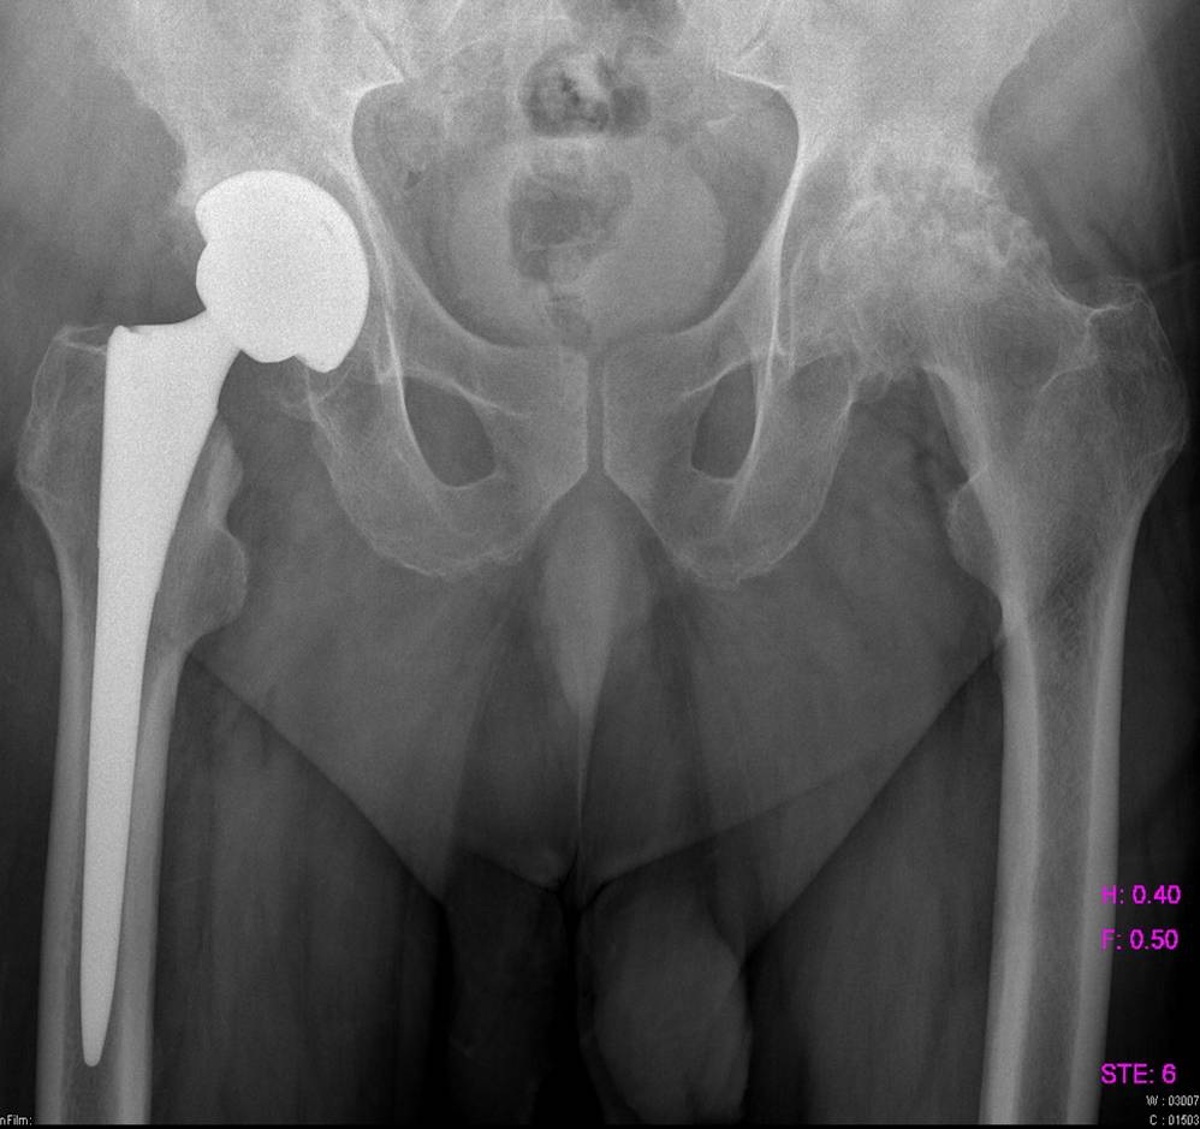

Диагностика ТБС рентгеном и асептический некроз: особенности лечения

Раздел: Снимки-откровения